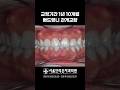

주걱턱 반대교합 치아교정으로 개선

주걱턱 반대교합 치아교정으로 개선

치아교정 주걱턱 양악수술 안면비대칭 턱비대칭 교정치료 교정치과 덧니 덧니교정 주걱턱교정 벌어진치아 과개교합 뻐드렁니 틀어진치아 앞니 앞니교정 앞니뒤틀림 앞니틀어짐 돌출입 임플란트 치아미백 신경치료 상악동거상술 뼈이식 통증 욱신거림 충치 크라운 보철 스케일링 잇몸 치약 칫솔 치과 사랑니 대전시청역 야간진료 교정전문의 잇몸치료 시린이 턱관절 턱관절장애 서울브라운치과 대전치과 대전치아교정 대전치아교정치과 둔산동치과 대전시청역치과 대전교정치과 대전임플란트 대전턱관절 대전치과잘하는곳 대전둔산동치과 치과병원 브라운TV 브라운티비 송창호 브라운치과